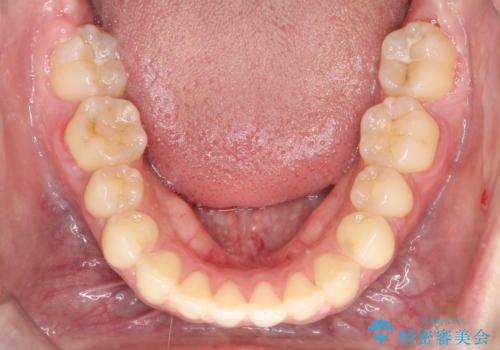

- 前歯の凸凹を主訴に来院されました。

予想治療期間2年でしたが、実際は1年半ほどで終了し満足していただきました。

小臼歯抜歯(上顎4番)して矯正治療を行なったことで、口元もスッキリしました。